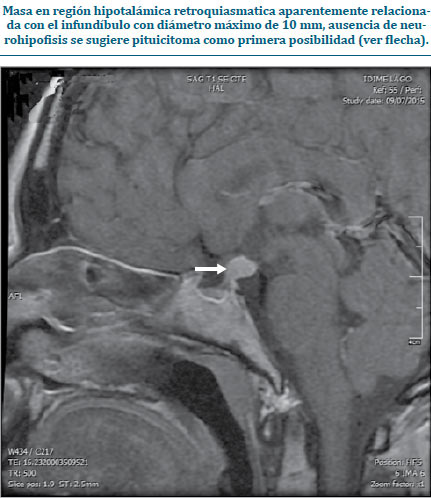

Al servicio de Endocrinología del Hospital de San José ingresa una paciente de género femenino de 26 años que consulta por polidipsia, poliuria, deshidratación mucocutánea, aumento de peso y cefalea persistente asociado a náuseas desde hace dos años, además refiere amenorrea sin galactorrea, sin respuesta a manejo médico planteado por ginecología. Con antecedente de hipotiroidismo en suplencia hormonal con levotiroxina 50 mcg/día. Al examen físico se evidenció mucosa oral seca y obesidad grado I (IMC 31,8). Consigo trajo reporte de RMN cerebral extrainstitucional que evidenciaba ausencia de neurohipófisis con presencia de pituicitoma (figura 2), además paraclínicos con hallazgos de densidad urinaria disminuida (1.003), hipernatremia (148 mEq/ml), hipercalemia (5,3 mEq/ml), hiperprolactinemia (143,8 ng/ml), TSH y T4 libre normales (3,36 mUI/L y 0,8 ng/ dl), (respectivamente con suplemento hormonal), estradiol disminuido (5 ng/L), cortisol a.m. en rangos normales (11,1 mcg/dL), somatomedina C normal (82,3 µg/L), FSH y LH disminuida (2,46 mUI/mL y 0,49 mUI/mL, respectivamente) y glucemia normal (87 mg/dL); por lo anterior se concluye que la paciente presenta hipogonadismo hipogonadotrófico con hipotiroidismo central y sospecha de diabetes insípida de origen central, secundarios a pituicitoma. Se consideró que hiperprolactinemia se debía a ubicación del tumor.

| Figura 2. RMN de silla turca contrastada |

A pesar de que no existen hallazgos radiológicos patognomónicos de esta lesión, la tomografía axial computarizada (TAC) y la resonancia magnética nuclear (RMN) ayudan a hacer una aproximación diagnóstica. En la TAC se puede encontrar una lesión sólida bien circunscrita, mientras que en la RMN se puede evidenciar una lesión isointensa en T1 e hiperintensa en T2(6,11), estos últimos compatibles con los hallazgos en nuestro caso número 1.